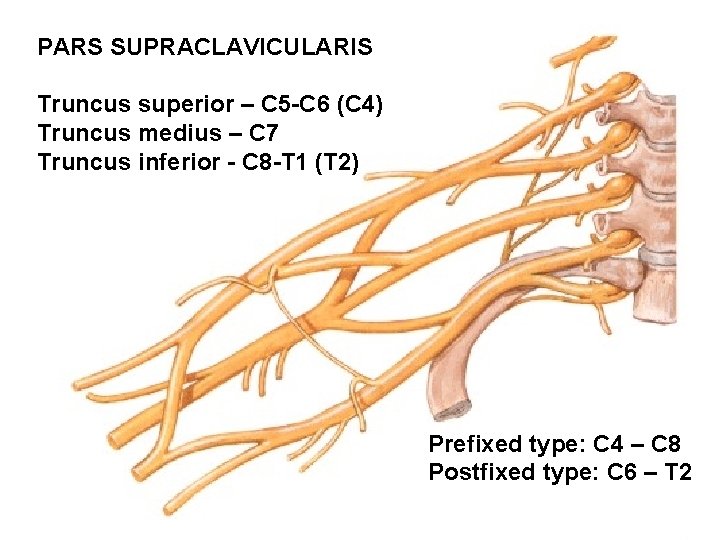

PARS SUPRACLAVICULARIS Truncus superior – C 5 -C 6 (C 4) Truncus medius – C 7 Truncus inferior - C 8 -T 1 (T 2) Prefixed type: C 4 – C 8 Postfixed type: C 6 – T 2